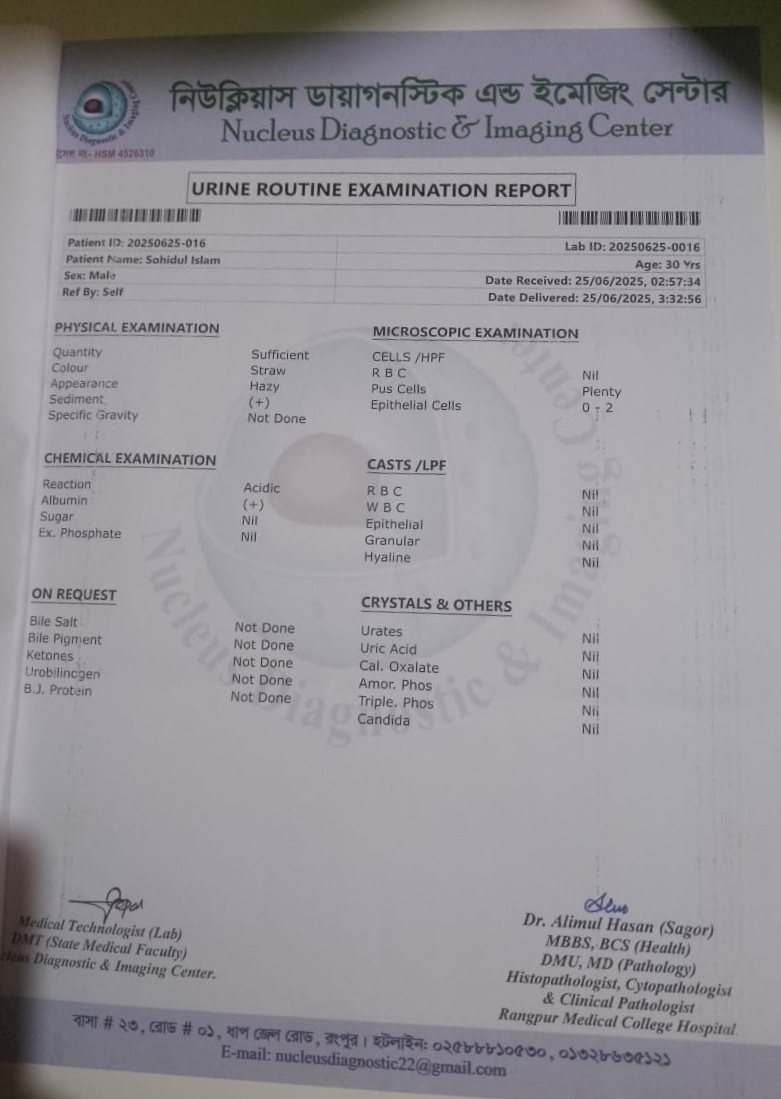

#250909I: জটিল কিডনি সমস্যায় আক্রান্ত শহিদুল ইসলাম চিকিৎসার জন্য সাহায্য চেয়েছেন, গ্রাম: মহব্বতপুর, জেলা: দিনাজপুর।